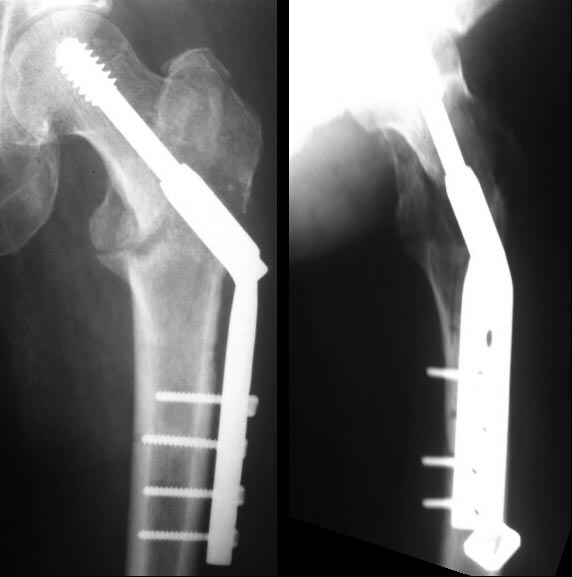

У нас в клинике, в мае 2015 года была прооперирована пациентка 50 лет,

страдающая сахарным диабетом, по поводу закрытого чрезвертельного

перелома левого бедра со смещением отломков. Был выполнен остеосинтез

левого бедра пластиной DHS. Через 3 недели после выписки, в проекции

дистального конца пластины сформировались 2 свища с серозно-гнойным

отделяемым. Через 1,5 месяца после операции пациентка была

госпитализирована в наше отделение. При поступлении у пациентки

отмечался умеренный отек мягких тканей в области левого бедра, два

свищевых хода с серозно-гнойным отделяемым. Гиперемии в области п\о

рубца не было. В отделение была проведена антибактериальная терапия

соответственно результатам посева. На фоне лечения свищи закрылись,

пациентка не лихорадит. Была выписана из стационара. Что делать дальше?

Оставить так и ждать сращения, которое в условиях инфекции и

нестабильной фиксации может и не наступить. Или же необходимо

оперативное лечение, какая тактика? К сожалению не могу предоставить

фистулограммы, но на них контраст распространяется вдоль пластины и

заполняет дефект в области большого вертела. Заранее спасибо!